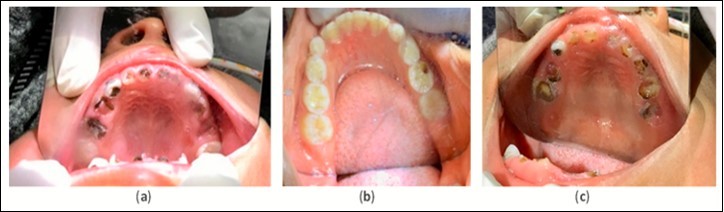

Figure 2.Example pre-treatment intraoral images for Ecuador (a), Ghana (b), and Bolivia (c) at initial evaluation.

The results discussed below are derived from Table 1. Please review the table for a more comprehensive evaluation of outcomes. Pre-treatment intraoral image examples of cavitated caries lesions in Ecuador, Ghana and Bolivia can be found in Figure 2. An example of arrested cavitated caries lesions can be found in Figure 3. All charted information for all patients was stored securely and confidentially and data was anonymized before evaluation of outcomes.

The treatment protocol involved carefully cleaning with a toothbrush and thoroughly drying all cavitated caries lesions using compressed air, followed by the application of 50% SN (Gordon Laboratories) by scrubbing with a microbrush then covering with FV (Centrix, Fluorodose) to protect from saliva contamination. The lesions received three separate treatments over two weeks. This protocol of three treatments was repeated at three and six months. Intraoral images were collected for the maxillary and mandibular arches for all children at each time point (Figure 2 and Figure 3). Emergency services were both conducted on-site and via referral to local professionals. Simple extractions of abscessed teeth with local anesthesia were done on site. Referrals to the local Ministry of Health Dental Clinics were done in cases where endodontics and complex restorative procedures were necessary.

The same materials, treatment frequency, and protocol used in Ecuador was replicated in Ghana. Evaluation and treatment were conducted at initial examination and at 12 months. Intraoral images of maxillary and mandibular arches were collected for all patients at each time point (Figure 2 and Figure 3) . At the 12-month visit, the Ghanaian dentist Dr. Ama Ofosu Appiah, our partnering individual, joined the Shoreview team and participated in the project. Her role was to assist in treatment and outcomes documentation. The Shoreview team calibrated this dentist in-person via hands-on training for the application protocol and cavitated caries lesion arrest assessment.

The treatment protocol used in Bolivia differed from what was used in Ecuador and Ghana. The protocol that was used involved the following: carefully clean the cavitated caries lesion using a toothbrush, thoroughly dry using compressed air, apply 38% SDF by scrubbing with a microbrush applicator, then cover with FV to prevent saliva contamination. Since access to electricity was available at the school, mobile dental equipment with a reliable compressed air source was available. This protocol was repeated at the timepoints of 6, 12, 18, 24, 30, and 36 months. Intraoral images of maxillary and mandibular arches were collected for all patients present at 36 months (Figure 2 and Figure 3). Emergency services were both conducted on-site and via referral to local professionals. If a tooth showed signs of being abscessed, it was extracted by Smiles Forever Clinic dentists on site using local anesthesia. Endodontics and complex restorative procedures were referred out to the local hospital dental department or the Smiles Forever Clinic in Cochabamba.